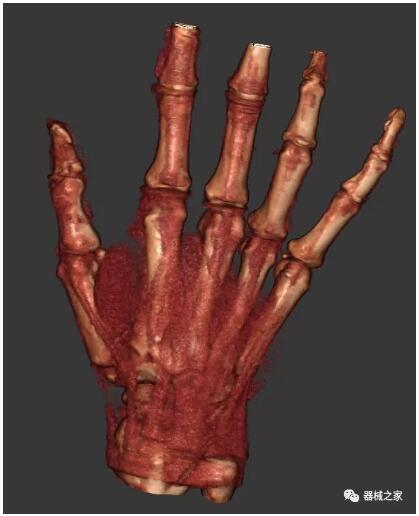

另外一款被稱為世界上最小的CT,它的重量?jī)H300磅,不僅能夠掃查足部,還可以檢查膝蓋和上肢等。

與上面介紹的CT一樣,它同樣具有輻射低、占地空間小(23*36)的特點(diǎn),隨開隨用(支持直接接入墻上的插座)。

這款CT使用非常方便,通過上下移動(dòng)保持與患者的手臂或者雙腿齊平,掃描快速,僅需要30秒左右就可以完成掃查。

以上介紹的CT均來自國(guó)外同一家公司,這些CT均配置了可視化軟件,可以進(jìn)行切片、3D重建以及大型CT附帶的所有典型的操作功能。

以下是這些“特立獨(dú)行”的CT所拍出來的圖像: